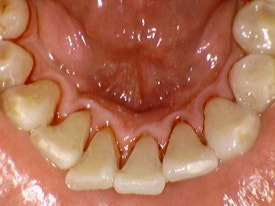

위 사진은 본원에서 진행한 스케일링 전 후 사진입니다.

보기만 해도 너무너무 시원하죠!